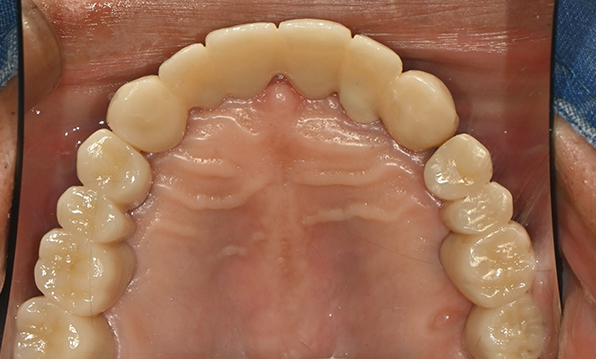

위 아래 치아가 정확하게 맞아야하는 고난이도 임플란트

임상 경험이 많은 숙련된 전문의의 섬세한 기술력이 중요합니다.

치료기간 : 2021.04.12~2021.09.15